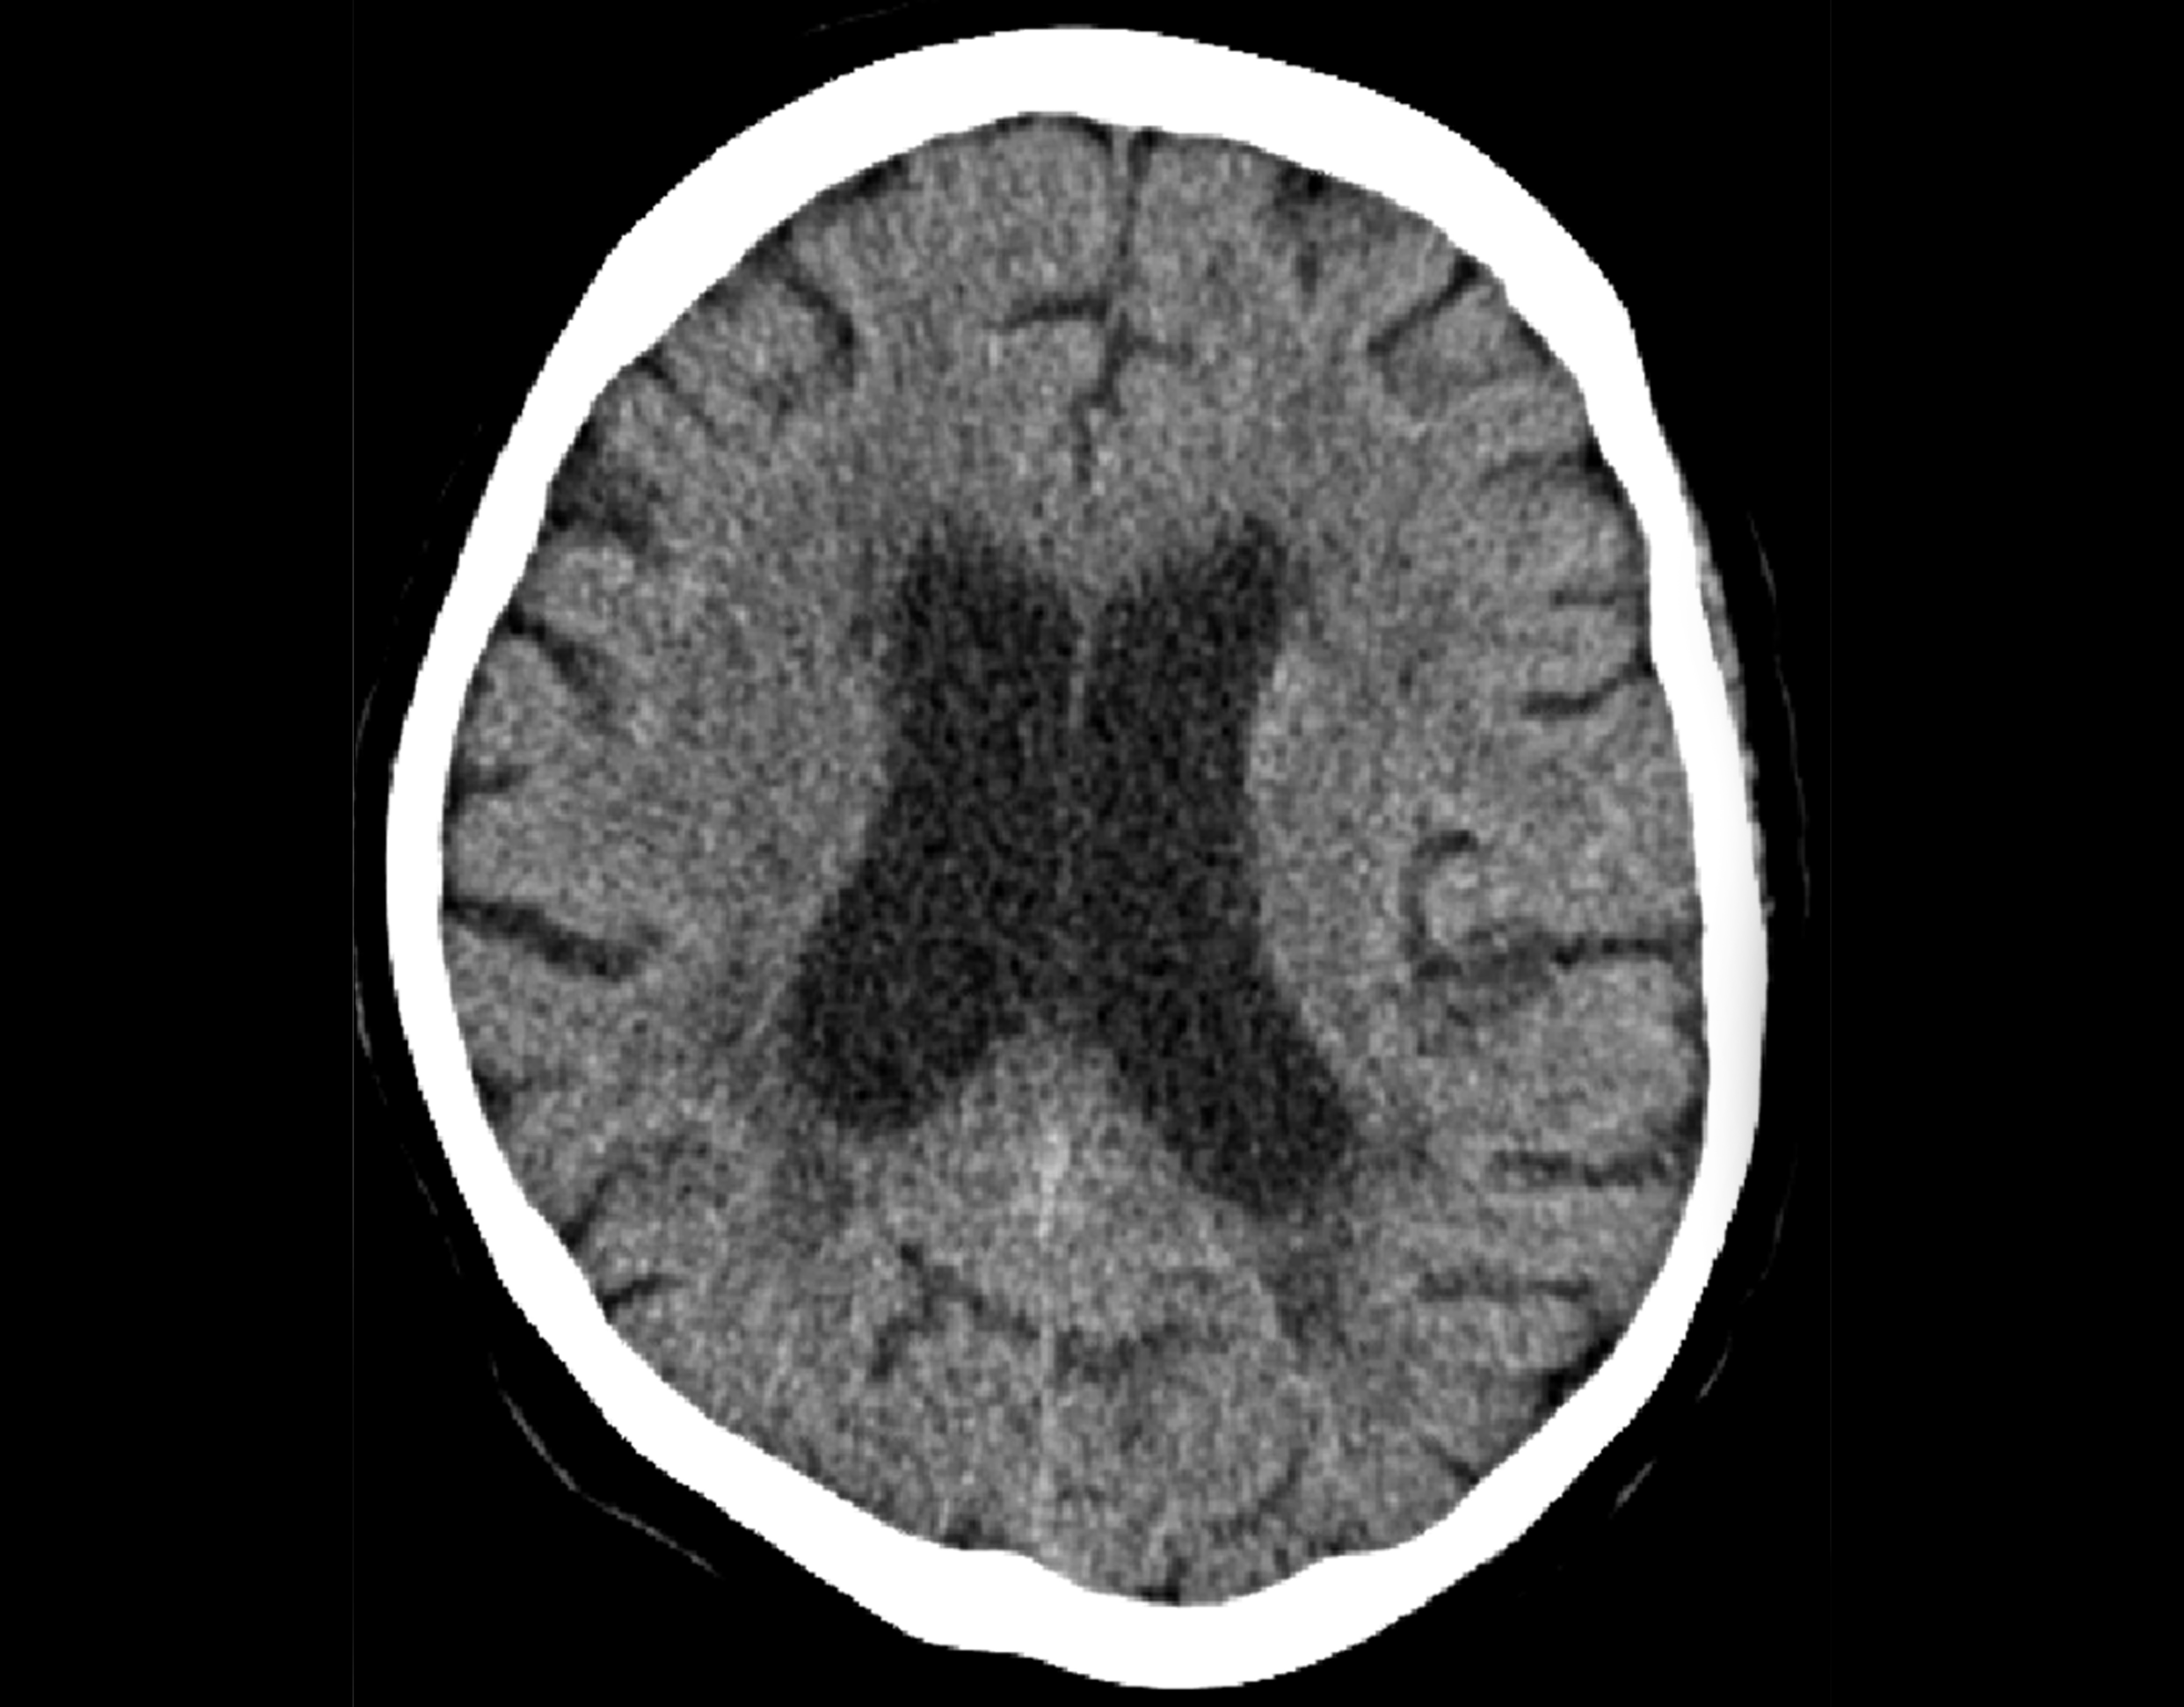

Electrocardiography showed sinus tachycardia. Neurologic examination revealed mydriatic pupils with direct and consensual pupillary light reflexes, muscular hypotension with no spontaneous movement and absent plantar reflexes, but no meningeal signs. Urinary analysis suggested a urinary tract infection. Brain computed tomography scan (Figure 1) excluded bleeding and infarct demarcation.

Figure 1. Brain computed tomography.